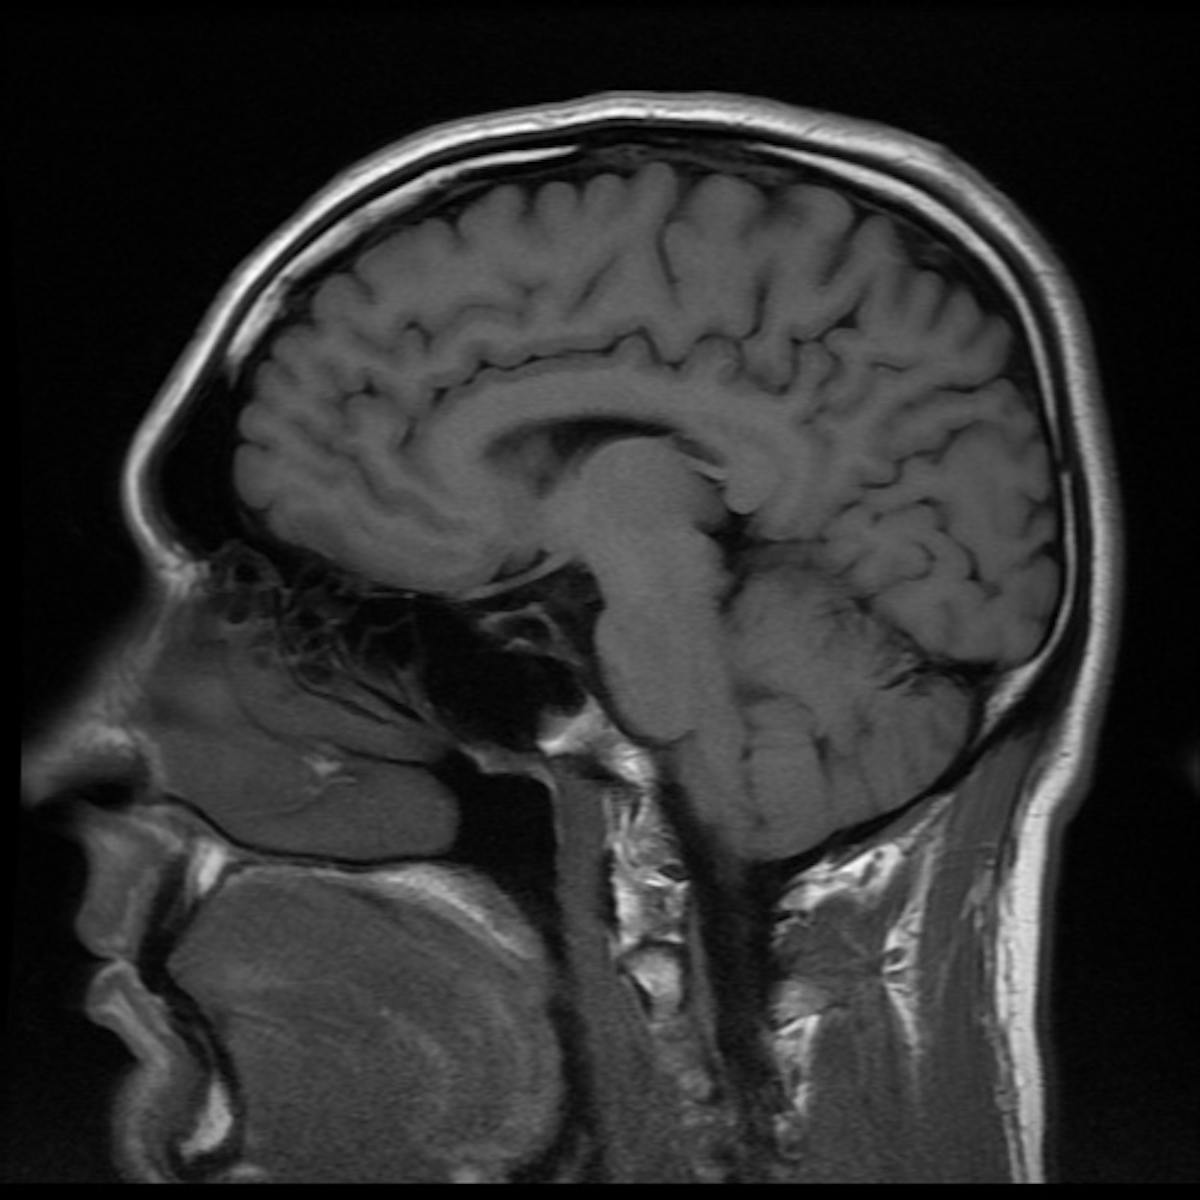

Brain Mri How To Read Mri Brain Scan Kenhub

Normal Brain Mri Radiology Case Radiopaedia Org